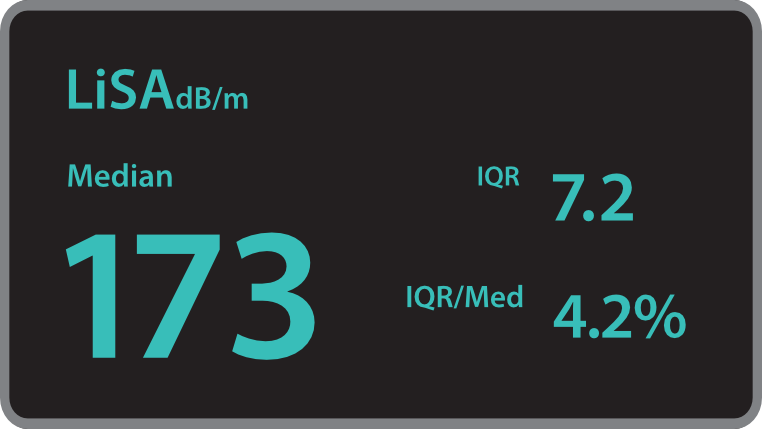

O Hepatus ÃĐ um equipamento de diagnÃģstico profissional n?o invasivo para doen?as hepÃĄticas que fornece resultados quantitativos que indicam o estÃĄgio da fibrose hepÃĄtica. Ele ÃĐ preciso, eficiente, confiÃĄvel e adequado ao acompanhamento de doen?as, abrindo uma nova era para o diagnÃģstico n?o invasivo de doen?as hepÃĄticas.

? aplicÃĄvel à triagem, ao diagnÃģstico, ao monitoramento e à avalia??o do tratamento da fibrose e da esteatose hepÃĄticas devido a vÃĄrios motivos. Especialmente durante o estÃĄgio inicial.